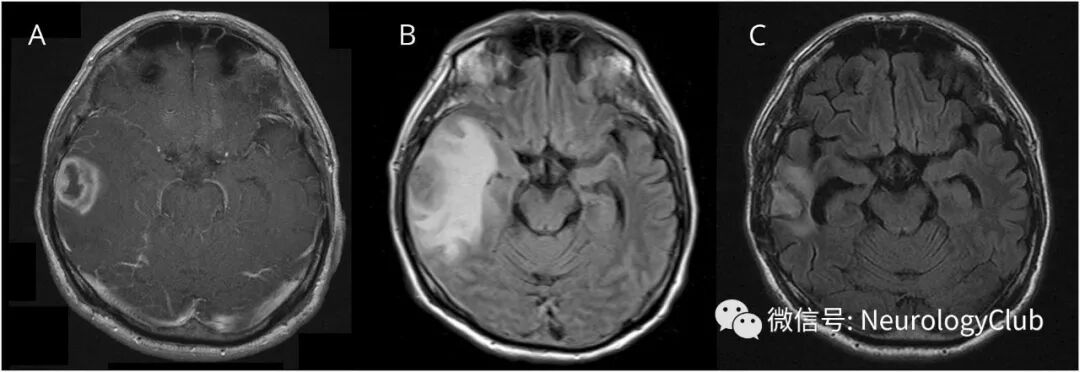

62岁HIV阴性男性患者,在入院前3年未发生过婚外性行为。本次因头痛就诊,头颅MRI可见一恶性肿瘤样环形强化病变(图1)。

(图1:T1增强[A]和FLAIR[B]可见右侧颞叶环形强化病灶伴大片水肿;C:瘤样病灶切除和术后抗菌治疗[青霉素G 6000000U/d,共14天,阿莫西林4000mg/d ,共14天]后3月复查,病灶明显改善)

切除肿瘤,免疫组织化学染色可见大量螺旋体(图2)。术后予抗菌药物治疗后病灶水肿明显改善。开始的血清快速血浆反应素(RPR)高出正常值155.6倍,梅毒螺旋体血凝反应高40960倍,荧光密螺旋体抗体吸收试验高1280倍,脑脊液RPR水平高出2.2倍,在超过6个月时间逐渐下降。

脑梅毒性树胶肿通常在梅毒感染10年后出现。MRI上可见单发或多发病灶,直径约2.0-2.5cm,位于大脑皮层及皮层下,T1像上病灶中心干酪样坏死为低信号或等、低混杂信号灶,T2像上干酪样坏死为高信号或等、高、低混杂信号,周围有较大面积水肿且有占位效应,增强扫描病灶呈不规则环形强化,可伴有邻近脑膜强化。尽管免疫组织化学染色很难发现单个螺旋体,但在侵袭性病例中可见大量螺旋体。